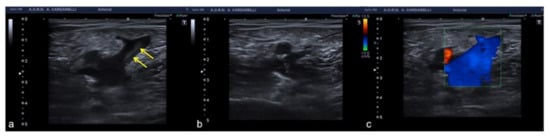

3.4. Anatomy and Anatomical Variants

Some anatomical structures and variances might yield difficult-to-interpret pictures, which can lead to errors if not fully understood [6]. The most insidious in emergency situations are pseudo-splenic hematoma (Figure 16 and Figure 17), pseudo-collections of pleural, pericardial, peritoneal, and retroperitoneal fluids (Figure 18, Figure 19, Figure 20 and Figure 21), and pseudo-pneumothorax related to abolished lung sliding due to the lung pulse or to patient apnea [6,7]. Others, such as hypertrophy diaphragmatic pillar (Figure 22), bladder pseudo-masses (Figure 23), inguinal pseudo-hernias (Figure 24), and the rouleaux phenomena, are generic, random, and highly conditioned (Figure 25). Often it is the emergency condition of the clinical context itself as well as the traumatic accident that could influence interpretational doubts or over-diagnosis with the necessity of more diagnostic confirmations, involving more costly complex examinations, an increased waiting time for the final diagnosis and medico-legal disputes [3,13].

Figure 24. Longitudinal US B-mode (a) and color-Doppler (b) scan of the inguinal canal show a blockage of the inguinal canal misinterpreted as an inguinal hernia with congested intestinal loop. On CT scan (c) it appears to be a right epididymitis with funiculitis.